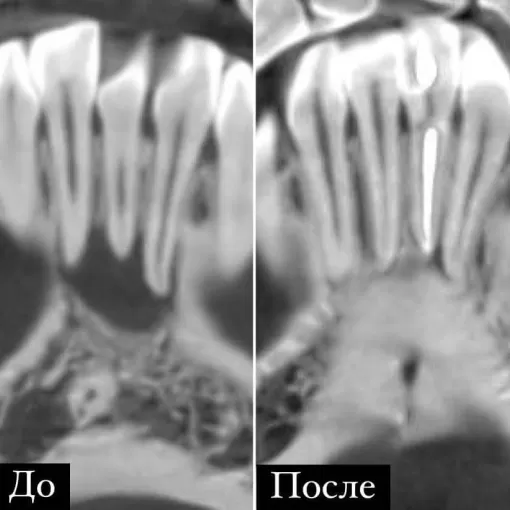

Клинический случай лечения "кисты" зуба 4.7

Стоматолог-терапевт Петрусенко О.А.

Пациент обратился с целью имплантации в области отсутствующего зуба 4.6. Однако после КЛКТ (3Д) исследования был обнаружен воспалительный процесс (киста) в области соседнего зуба 4.7 (рис. 1).